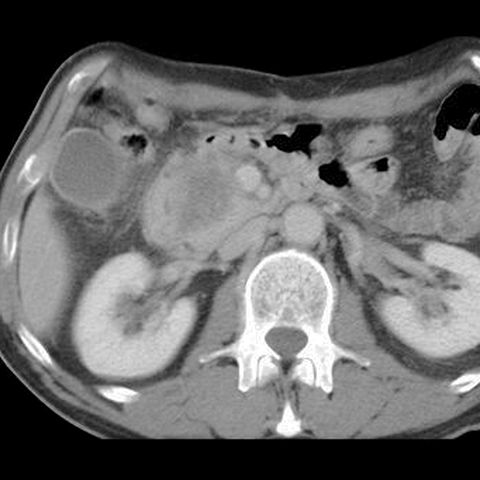

65-year-old male presents with painless jaundice. [4 of 5]